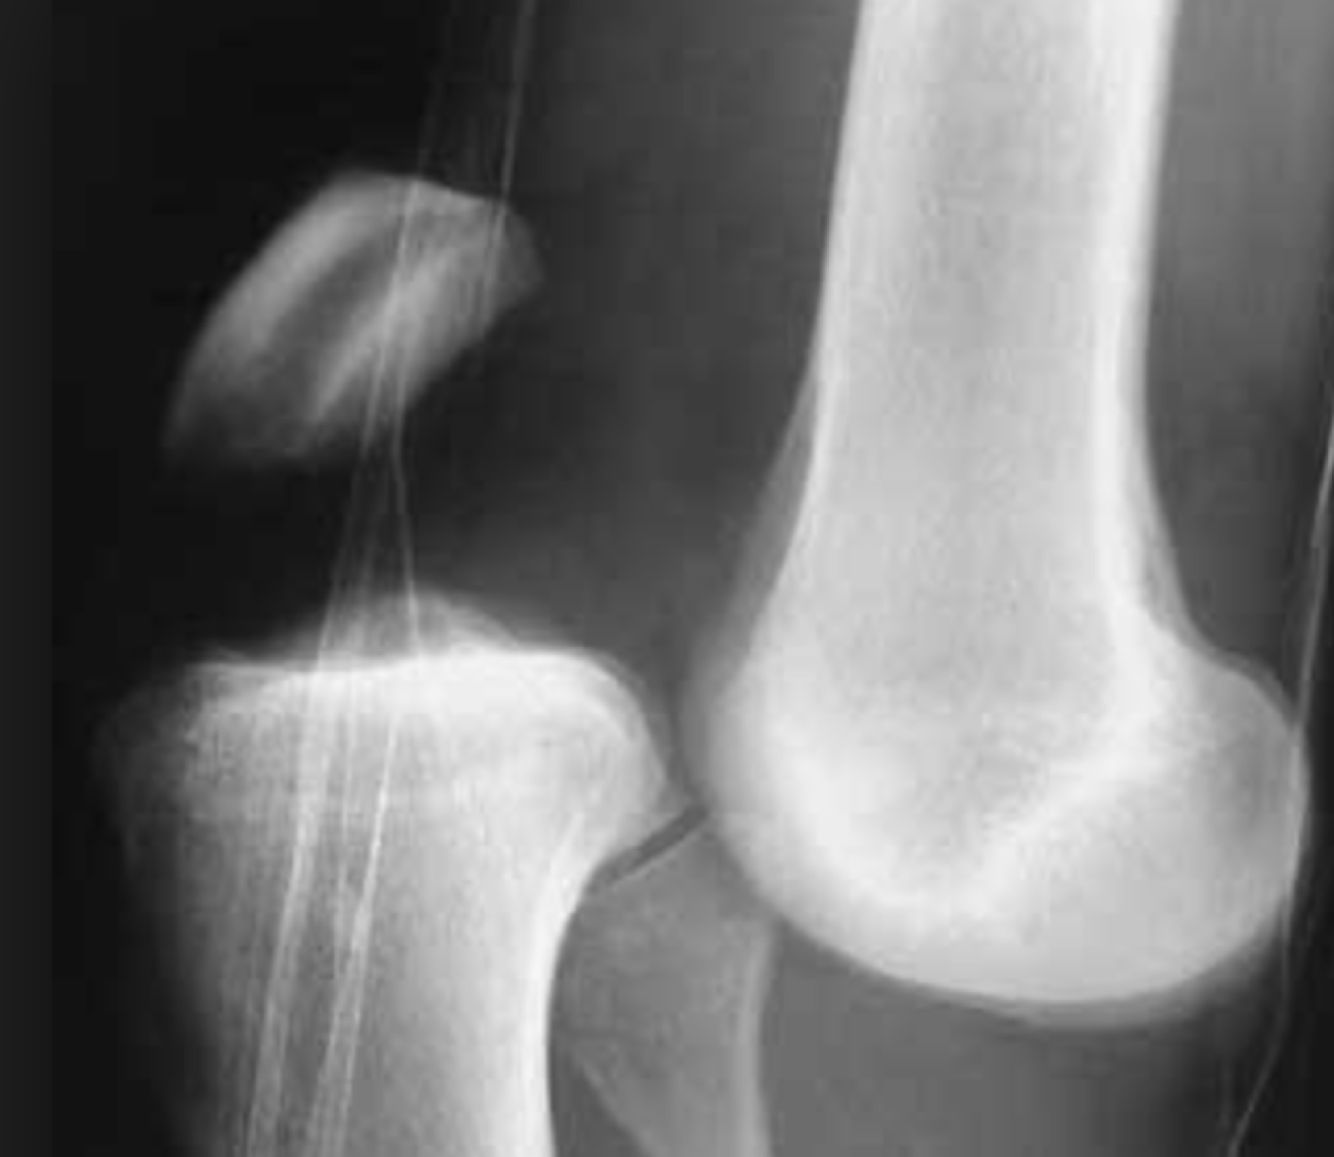

What does this radiograph show?

Knee dislocation